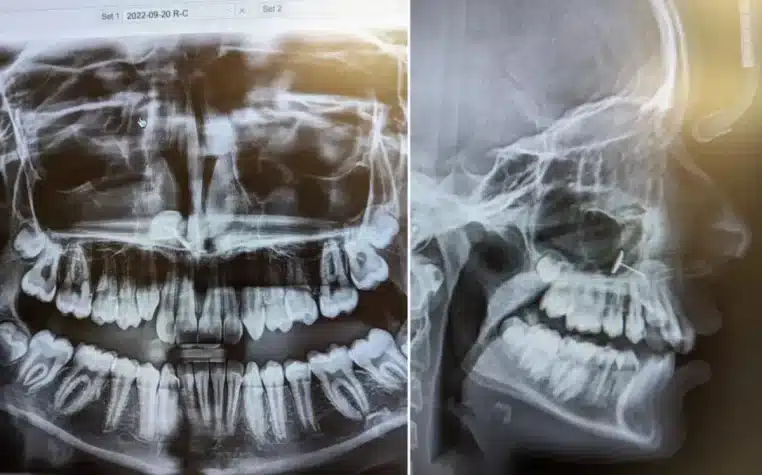

« L’orthodontiste est entré dans la salle et a affiché les radios sur l’écran », raconte la maman à Newsweek. « Nous les avons vues en même temps et pendant plusieurs minutes, nous avons essayé de comprendre ce que nous étions en train d’observer. »

Sur l’image, un petit objet métallique apparaissait, coincé dans les sinus de la fillette. La mère était stupéfaite et n’avait aucune idée de ce que cela pouvait être. Mais une personne dans la pièce savait exactement ce qu’il s’était passé : sa fille.